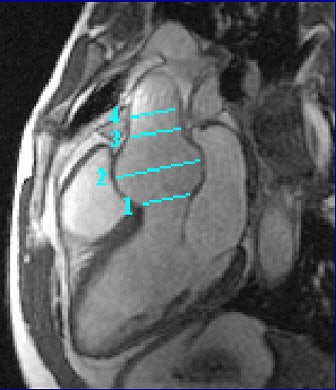

| Two-dimensional, steady state free precession cine MRI acquired during diastole, including the four locations for aortic root measurements. Image and caption courtesy of Dr. Alan Stolpen, Ph.D. |

For both modalities, the aortic root was imaged in the parasternal long-axis plane. Standard measurements were obtained at the aortic annulus, sinuses of Valsalva, sinotubular junction, and proximal ascending aorta. The Bland-Altman analysis was used to assess agreement between TTE and MRI.